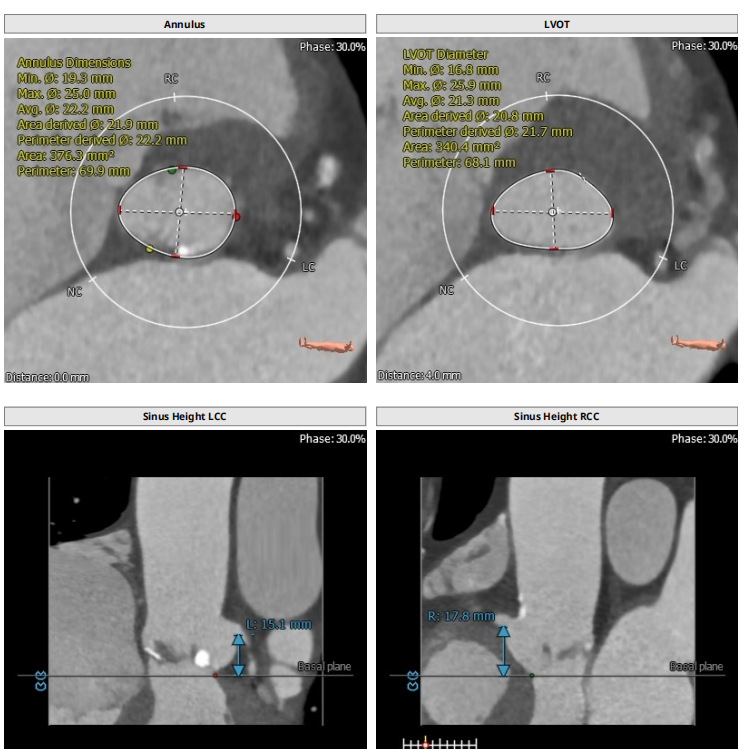

根部解剖: